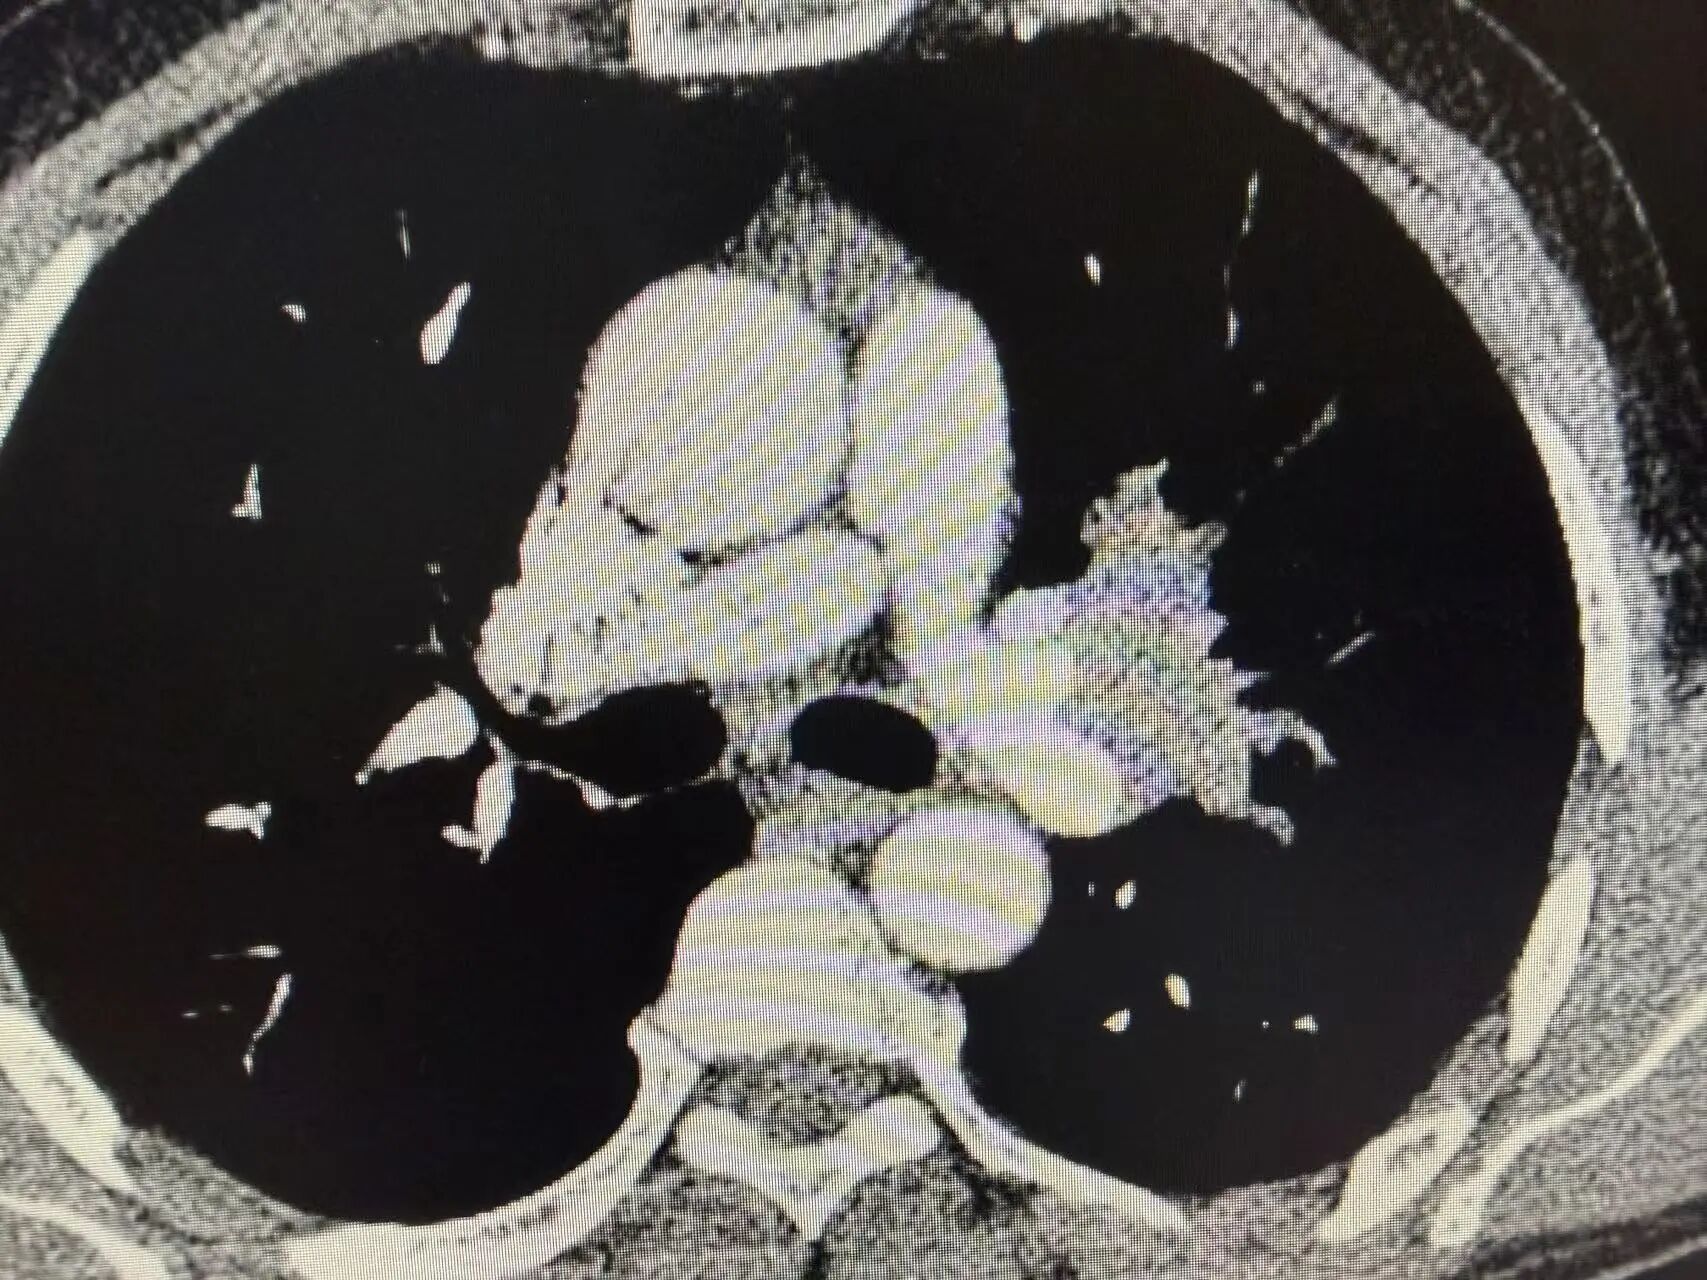

1-2.jpg

1-3.jpg

新辅助治疗前CT:可见左上肺中央型占位,肿瘤侵犯血管

1-4.jpg

1-5.jpg

新辅助治疗后CT:肿瘤明显缩小